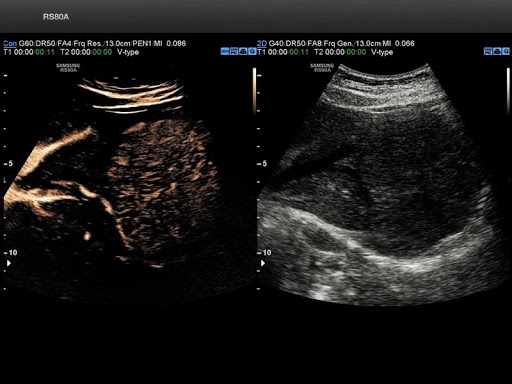

- Качество изображений: сканер оснащен модулем гибридного формирования луча Hybrid Beamforming Engine evo. Создает точный ультразвуковой сигнал и улучшает изображение.

- Четкость изображений: система снижает уровень шума и делает визуализацию при помощи функции SDMRevo отчетливей. Сканер UGEO RS80A использует монокристаллические УЗИ датчики работающие по технологии Single Crystal для увеличения глубины проникновения в ткани и разрешающей способности устройства.

FSI (Full Spectrum Imaging) - это многоступенчатый алгоритм получения избирательного контрастирования изображения по всей глубине сканирования. Комбинирует ультразвуковую информацию от акустических полос разной частоты, снижая количество артефактов. Делает лучше B- изображения за счёт ширины спектра ультразвуковой волны.

Тканевая гармоника увеличивает порог приема частоты обратного сигнала, тем самым улучшает качество изображения в В-режиме (серошкальном). Полезна в условиях плохой визуализации. Помогает точно поставить диагноз у людей с лишним весом или большой мышечной массой.

PIH (пульс-инверсная гармоника) - дает резкость и четкость визуализации, помогает лучше верифицировать кисты. Это достигается за счет улучшения видимости и четкости границ органов.